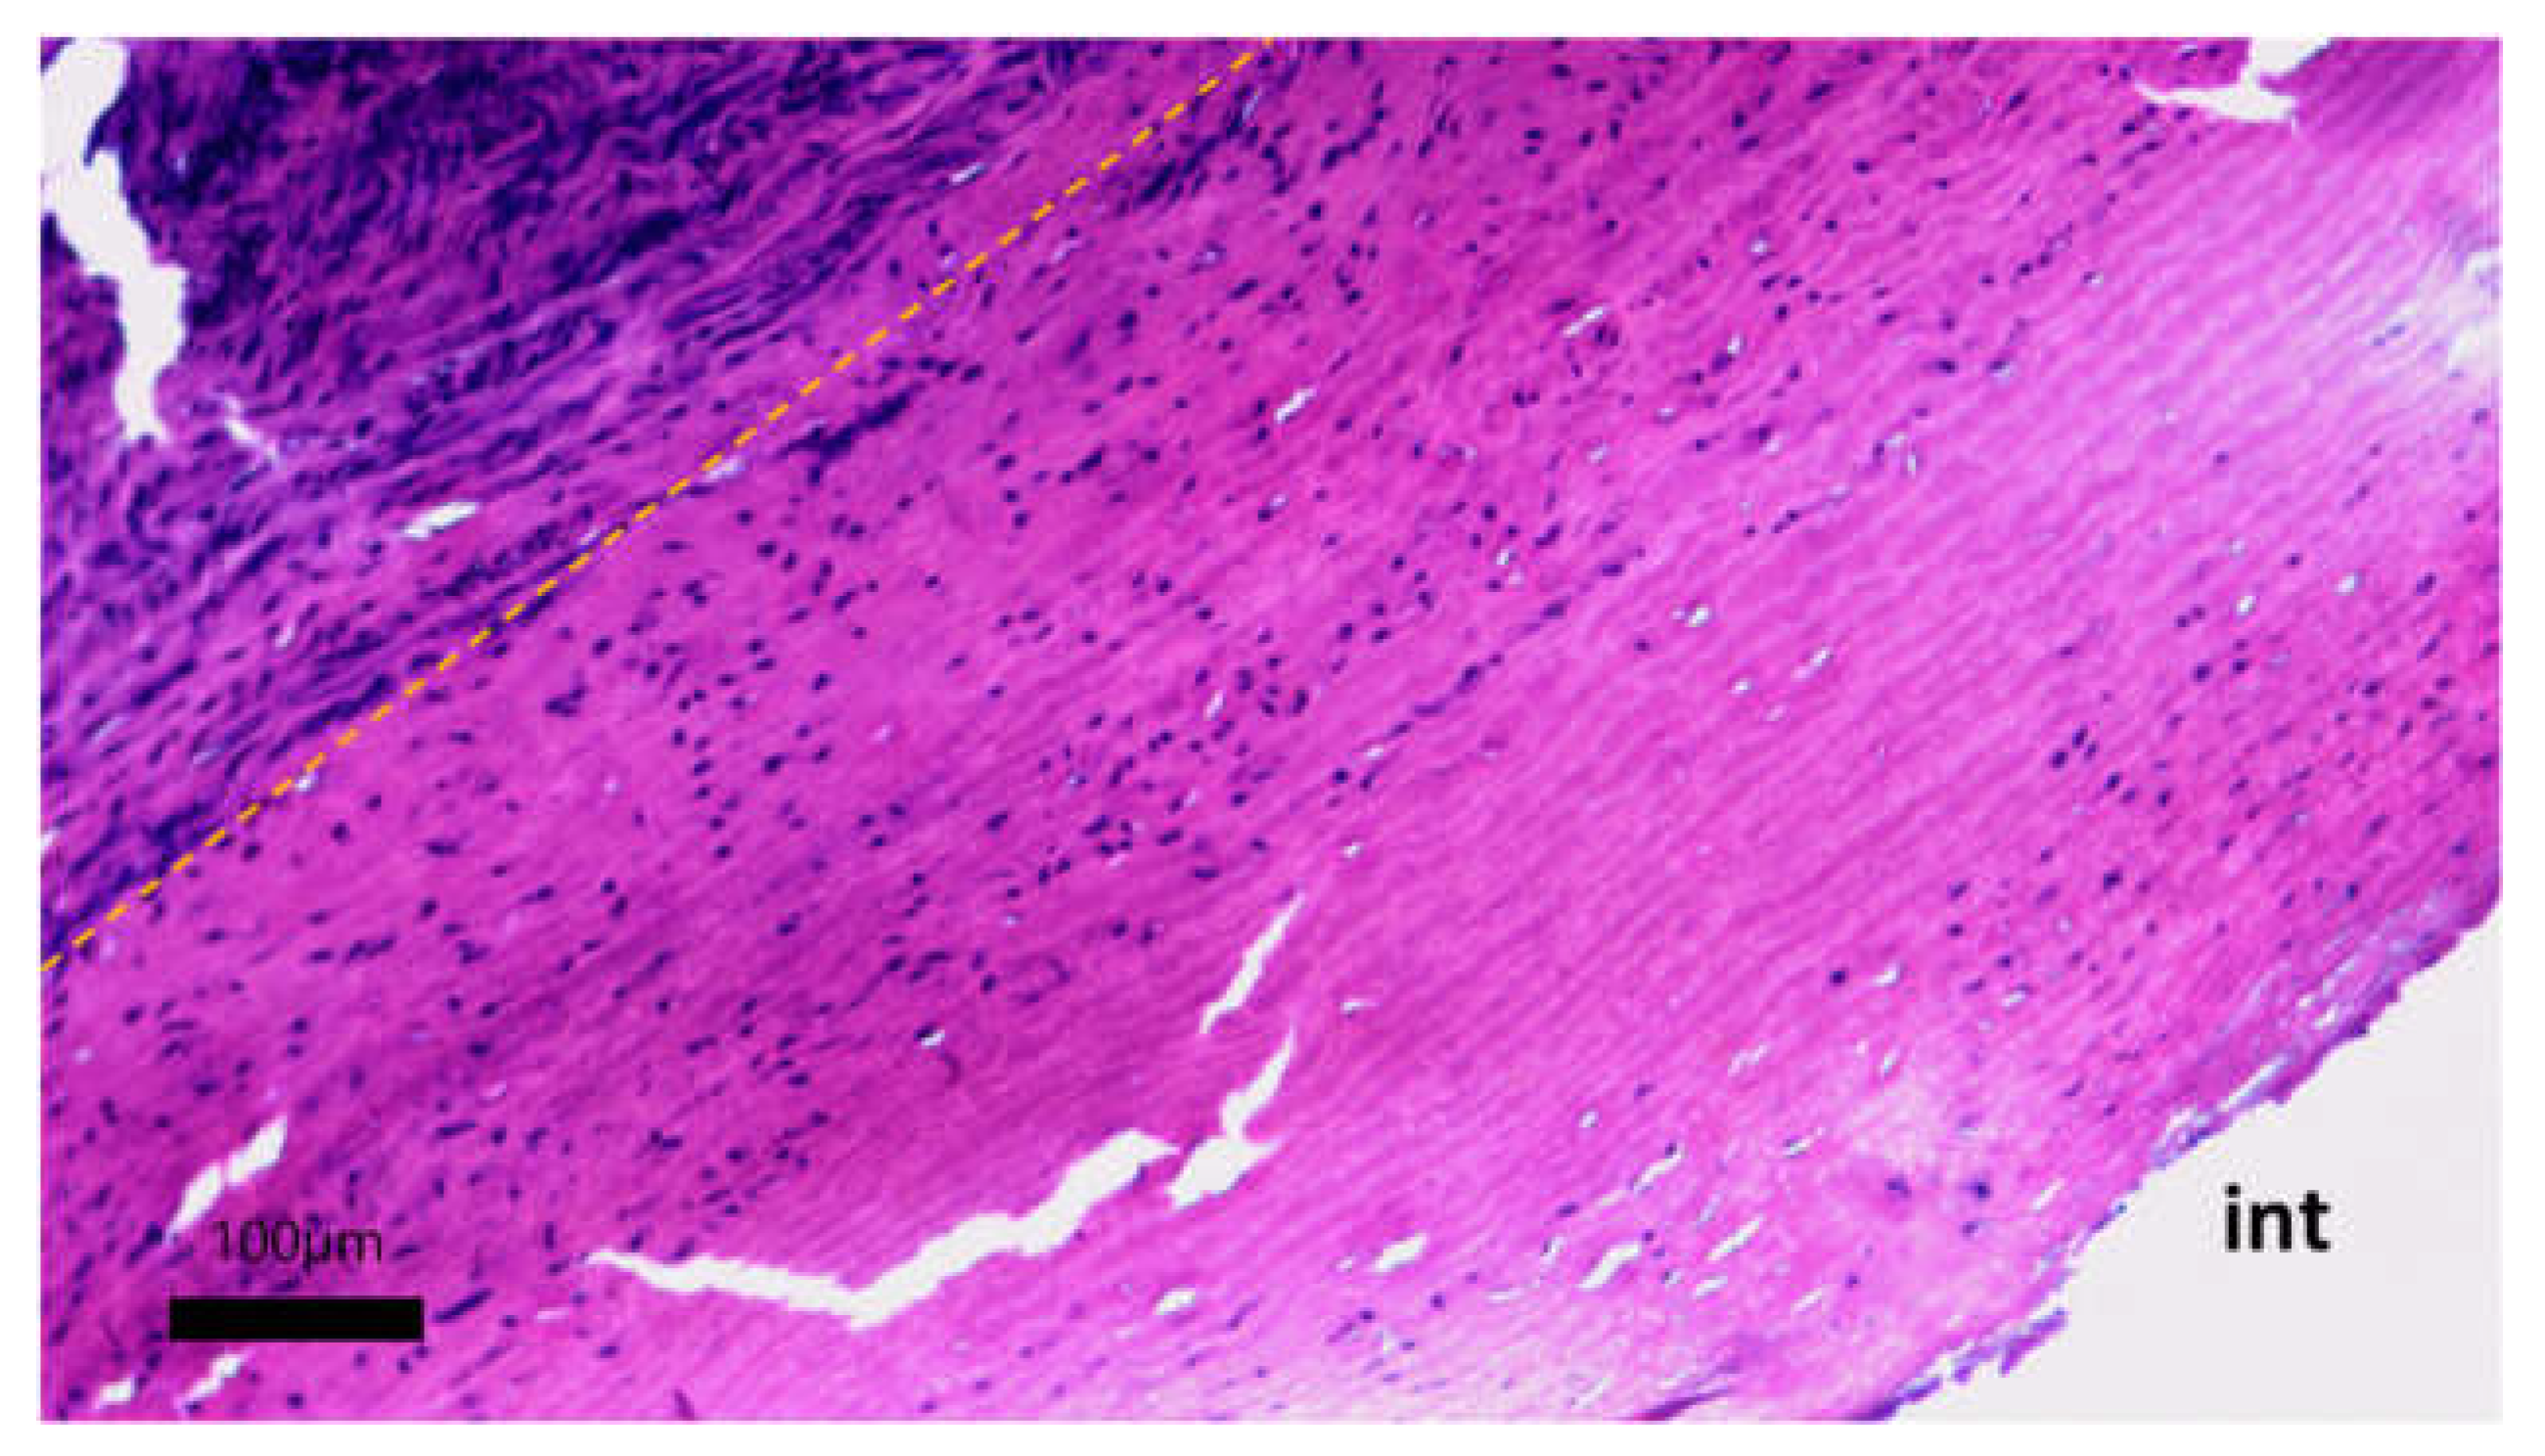

The formation of a neointimal layer is noted directly in the anastomosis zones with further spread to the tissue of the vascular graft. Laser treatment did not have a negative effect on the permeability of the vascular graft wall for fluid. Microscopic examination of the developed vascular prostheses after 30 days of implantation in pigs revealed the initial stages of colonization of the cell-free stroma of the graft with fibroblast-like cells (Figure 12).

On the micrographs, there were no zones of inflammation with foci of lymphocytic infiltration, and no signs of thrombus formation on the surface of the vascular graft were found. The tissue of the prosthesis does not differ in its structure from the original one, the packing of collagen fibers is dense, the waviness of elastic fibers is not disturbed, and no zones of loosening were found. The stroma of the graft is populated by small fibroblast-like cells (Figure 13).

Figure 12. Cellular migration into the stroma of the vascular prosthesis: hematoxylin-eosin staining, scale bar 100 μm. Yellow dotted line - the boundary of the implanted vascular graft and the newly formed adventitial tissue; int - intimal side of the vascular graft.